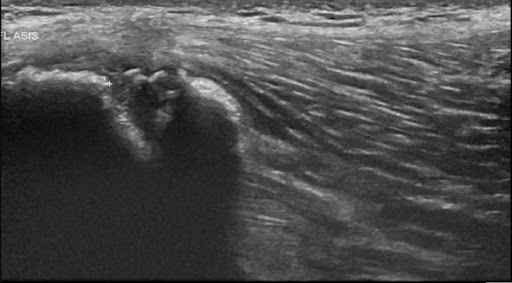

The below X-ray (2) and ultrasound images are from a young teen footballer with an acute, painful ‘pop’ over the high left lateral hip on landing from a jump.

He struggled to bear weight and retired. Examination revealed him unable to single leg squat, Tensor Fascia Lata loading and oblique crunches were sore; exquisitely tender with swelling over 8cm of the iliac crest to the anterior superior iliac spine.

Figure 8 and 9 revealed avulsion of the iliac crest apophysis – rare!!

Figure 8 – AP pelvis xray

Figure 9 – Ultrasound iliac crest